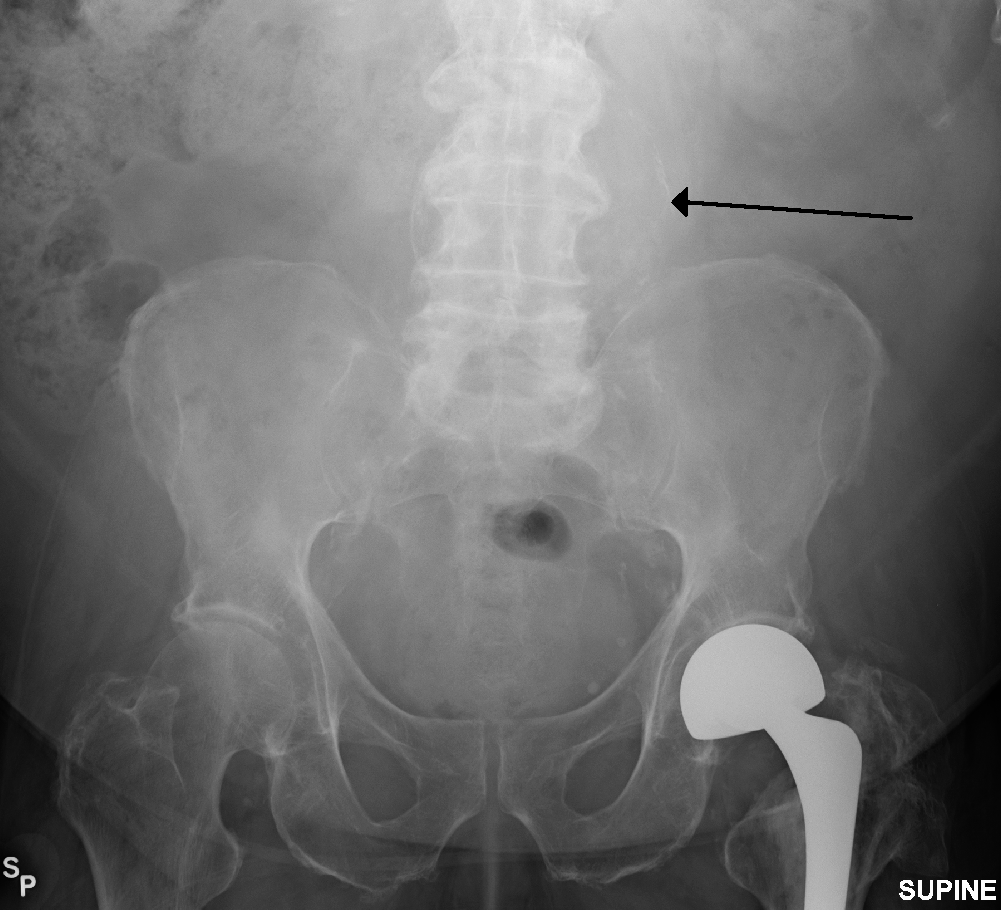

복부대동맥류는 일반적으로 신체 검사, 복부 초음파 검사, CT 스캔으로 진단된다. 단순 복부 방사선 사진은 대동맥벽이 석회화된 경우 대동맥류의 윤곽을 보여줄 수 있지만, 전체 대동맥류의 절반 미만에서만 확인 가능하다.복부 초음파 검사는 대동맥류를 선별하고, 대동맥류가 있는 경우 그 크기를 결정하는 데 사용된다. 또한, 복강 내 자유 액체도 감지할 수 있다. 이는 비침습적이고 민감하지만, 장내 가스나 비만은 유용성을 제한할 수 있다.[29] CT 스캔은 대동맥류에 대해 거의 100%의 민감도를 가지며, 해부학적 구조와 혈관 내 복구 가능성을 상세히 설명하여 수술 전 계획에도 유용하다. 파열이 의심되는 경우, 후복막강 내 체액도 신뢰할 수 있게 감지할 수 있다. 대동맥류를 시각화하는 데 덜 사용되는 대체 방법으로는 MRI와 혈관조영술이 있다.[30]

복부 대동맥류는 일반적으로 신체 검사, 초음파 또는 CT 스캔으로 진단된다. 복부 방사선 사진은 동맥벽이 경화되었을 때 동맥류의 윤곽을 보여주지만, 동맥류 절반 이하에서만 확인 가능하다. 초음파 검사는 동맥류 검사 및 동맥벽 크기 결정에 사용되며, 자유 복막액이 검출될 수 있다. 하지만 장내 가스나 비만은 검출을 어렵게 할 수 있다. CT 스캔은 동맥류에 대해 거의 100% 확신을 가지기 때문에 수술 전 계획에 유용하며, 파열이 의심되는 경우 복막 후방 액체를 확실하게 감지할 수 있다. MRI 및 혈관 조영술도 사용 가능하지만, 자주 사용되지는 않는다.[119]